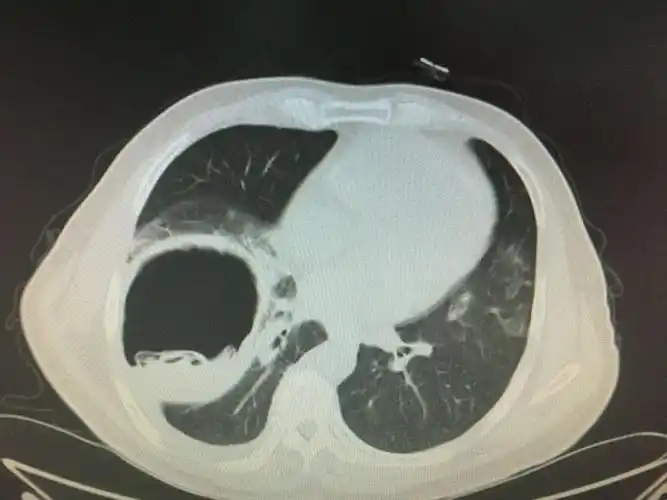

左肺下叶,肺包虫病,2016/12/07【河南病理交流群病例3】

左肺下叶肺包虫病20161207河南病理交流群病例3

肺内包虫

肺包虫病一例——黄超,新疆职业病医院

肺包虫囊肿